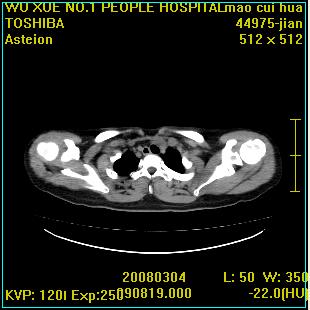

标题: CT12025:男,50岁,左肩活动受限半年。 [打印本页]

标题: CT12025:男,50岁,左肩活动受限半年。

肩关节骨质破坏呈小囊状,其周软组织轻度肿胀,余未见异常。

考虑:肩袖损伤。建议mri。

左侧肱骨头密度不均匀,高低混杂,周围软组织略肿胀,考虑结核性病变。

左侧肱骨头密度不均匀,高低混杂,髓腔密度稍高,周围软组织略肿胀,肌间隙模糊,考虑慢性骨髓炎可能。密切结合临床!